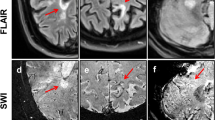

In all patients, MR images were evaluated in consensus by two readers (with 2 and 15 years’ experience respectively). If uncertainty remained regarding potential lesion classification, an additional reviewer (with 30 years’ experience) was consulted for final determination of lesion classification. On baseline MRI, acute CELs were identified on post-contrast T1-weighted images. To minimize partial volume effects only supratentorial lesions ≥ 5 mm in their longitudinal axis entered further analysis. According to their topography, lesions were classified as periventricular, deep white matter or juxtacortical (located in the frontal, parietal, temporal or occipital lobe) [10]. Pattern of contrast-enhancement was categorized as “nodular” or “ring-like” as suggested previously [11,12,13]. ADC maps were assessed for the presence of a peripheral hypointense rim [14]. Figure 1 demonstrates representative examples. The initially CELs were identified on follow-up MRI and investigated for the presence of a hypointense rim on SWI [15]. In cases hypointense ring-like signals or “dots” at the lesion edge were visible on at least two contiguous slices, the initially CEL was defined as an IRL, otherwise as a non-IRL. In addition, SWI minimum intensity projection images were carefully evaluated to guarantee that venous vessels at the lesion edge were not mistaken for part of iron rims. Furthermore, susceptibility-weighted images were evaluated for the presence of the central vein sign (CVS) according to the “North American Imaging in Multiple Sclerosis Cooperative” (NAIMS) criteria [16].

Representative examples of the observed contrast-enhancement and apparent diffusion coefficient (ADC) patterns of acute multiple sclerosis lesions. From left to right: Baseline post-contrast T1-weighted images and baseline ADC maps. Fluid-attenuated inversion recovery (FLAIR) and susceptibility-weighted images (SWI) at follow-up. A Nodular enhancement without a hypointense rim on ADC maps. On follow-up MRI after 9 months, no iron rim is detectable. B Nodular contrast-enhancement with a hypointense rim on ADC maps (arrows). On follow-up MRI after 3 months, no iron rim is detectable. C Ring-like enhancement with a hypointense rim on ADC maps (open arrowheads). On follow-up MRI after 6 months, no iron rim is detectable. D Ring-like enhancement without a hypointense rim on ADC maps. Note the iron rim on follow-up after 14 months (dotted arrows)